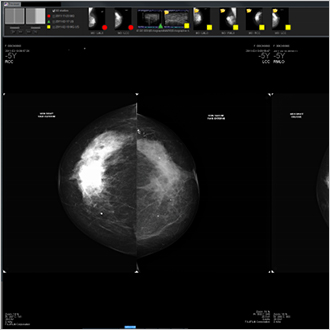

TM-Mammo

La solution TM-Mammo a été spécifiquement développée pour répondre aux besoins de stockage, de distribution et de diagnostic de l’ensemble de l’imagerie mammographique digitale produite au sein des services de sénologie. Le viewer TM-Mammo permet une comparaison facile avec l’historique multi-images du patient (de tous types de modalités) et une visualisation des séquences d’affichage propres à l’utilisateur. La tomosynthèse fait partie intégrante des séquences d’affichage.